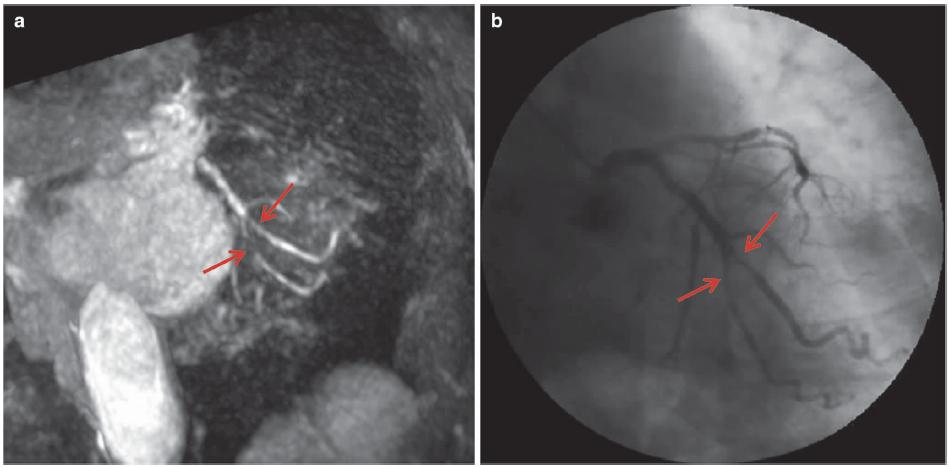

图7.9 心肌缺血,LCX明显狭窄。患者女性,78岁,胸痛。注射0.15mmol/kg钆喷酸葡胺后,通过使用平衡相中的脂肪饱和脉冲获得梯度回波三维CMRA图像(TR/TE,4.2/2.1ms;翻转角度,20°;SENSE因子4;FOV 280mm×280mm×120mm;采集矩阵256×256×80;重建矩阵512×512×160)。

(a)全心冠状动脉MR造影MIP图像显示LCX(箭头)明显狭窄。(b)冠状动脉MR造影与冠状动脉造影(箭头)之间存在良好的一致性。